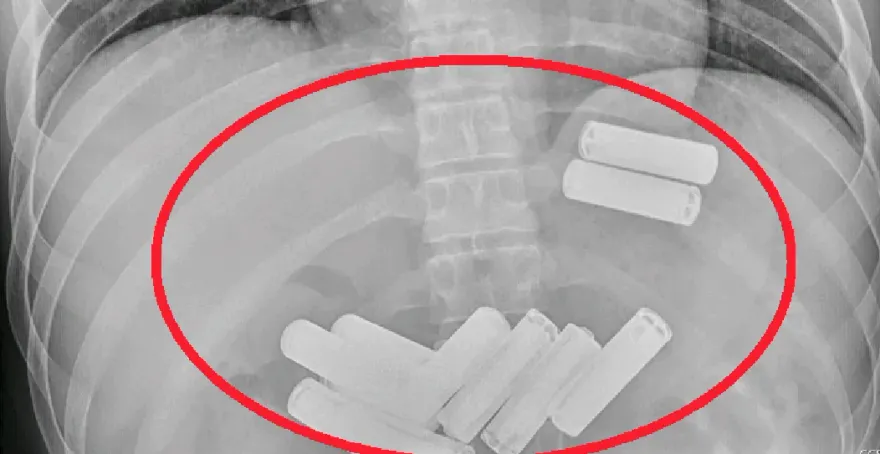

大千醫院

苗栗

電池

胃部

胃鏡

誤食異物

吞下肚

食道撕裂